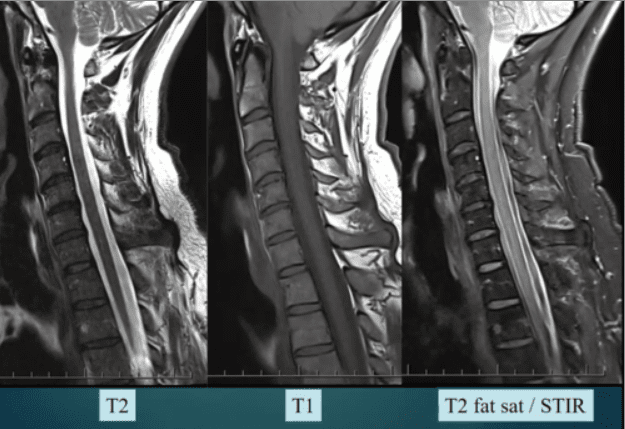

1.2 Decoding the Spinal Pathologies: T1, T2, STIR, and the Critical Role of Edema

Effective MRI interpretation depends on a deep understanding of various pulse sequences and their physiological meanings (Advanced MRI Interpretation of Spinal Pathologies, n.d.). Our team meticulously reviews the T1-weighted, T2-weighted, and Short Tau Inversion Recovery (STIR) sequences to build a precise picture of tissue health, fluid content, and fat presence (Spinal Diagnostics, n.d.).

- T1-Weighted Images: Best for visualizing anatomy and fatty tissue (which appears bright).

- T2-Weighted Images: Best for visualizing fluid (which appears bright), making them excellent for identifying edema and inflammation.

- STIR (Short Tau Inversion Recovery): A crucial sequence that suppresses the fat signal, making it highly sensitive for detecting bone marrow edema and interstitial fluid (inflammation) that is masked by fat on T1 or T2 sequences (Spinal Diagnostics, n.d.).

The presence of edema (abnormal fluid accumulation) in the bone marrow or soft tissues surrounding the spine is a powerful, objective indicator of acute trauma. Edema is the body’s immediate inflammatory response to injury and provides the temporal signature required for injury dating.

- MRI Appearance: On T1-weighted images, it looks dark (hypointense), and on T2/STIR-weighted images, it looks bright (hyperintense) (Spinal Diagnostics, n.d.).